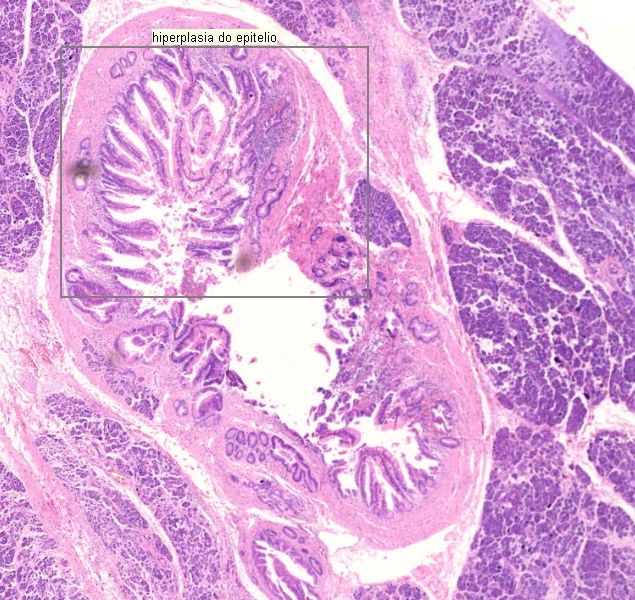

1. Adenocarcinoma ductal (4210H)

1. Atipia celular

1. Infiltração perineural

1. Desmoplasia

1. Glândulas com padrão infiltrativo